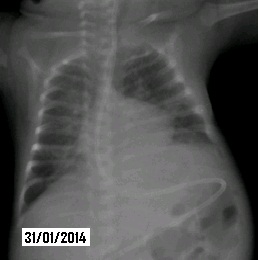

A fisioterapia vem assumindo seu papel indispensável na equipe assistencial na Unidade de Terapia Intensiva neonatal. O presente estudo relata a experiência positiva no desmame de um recém nascido prematuro que inicialmente apresentou moderada atelectasia à direita sendo revertida, e após sua extubação apresentou importante atelectasia nos dois terços inferiores do pulmão esquerdo devido a uma paralisia diafragmática unilateral, confirmada pelos achados ecográficos. A equipe da cirurgia pediátrica orientou aguardar uma semana para observar evolução pulmonar, no entanto se a evolução pulmonar fosse negativa com permanência de áreas atelectasiadas haveria indicação de cirurgia de plicatura do diafragma esquerdo. A escolha de técnicas de fisioterapia respiratória adequadas favoreceu a reexpansão pulmonar de áreas com atelectasias, sendo possível realizar o desmame da ventilação mecânica não invasiva e manter o bebê em ar ambiente. O recém nascido teve alta hospitalar com padrão ventilatório eficaz, mamando no seio materno e sem necessidade de intervenção cirúrgica.